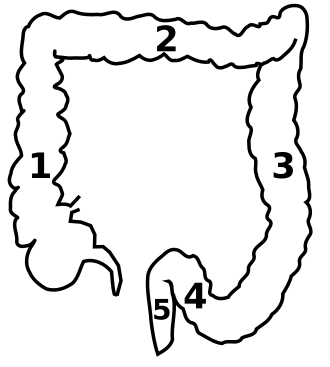

(1) Aufsteigender Grimmdarm (Colon ascendens)

(2) Querverlaufender Grimmdarm (Colon transversum)

(3) Absteigender Grimmdarm (Colon descendens)

(4) Sigma (Colon sigmoideum)

(5) Mast- oder Enddarm (Rectum) und Anus.

Es fehlt die Markierung für den in der linken unteren Bildhälfte befindlichen Blinddarm (Caecum) mit anhängendem Wurmfortsatz (Appendix).